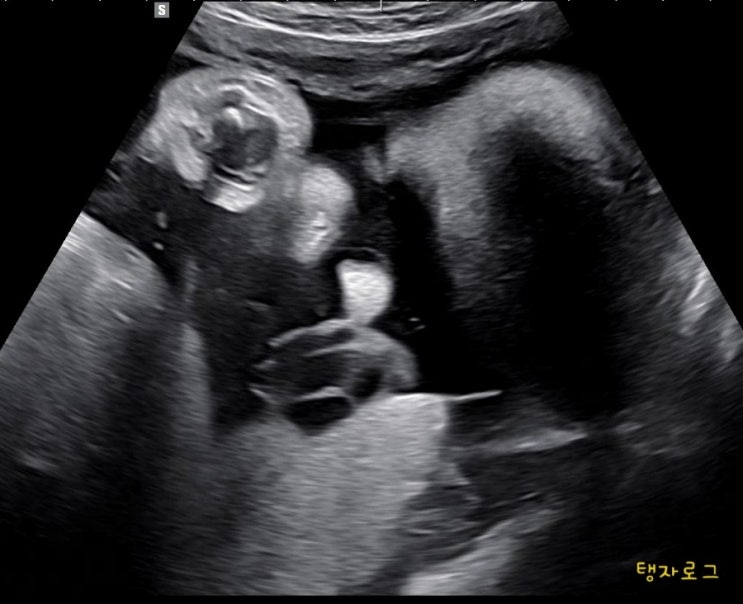

안녕하세요 임신 38주 2일차에 초음파 사진이 아닌 실제로 망고를 보게 된 망고어멈이에요 ?? 2022년...